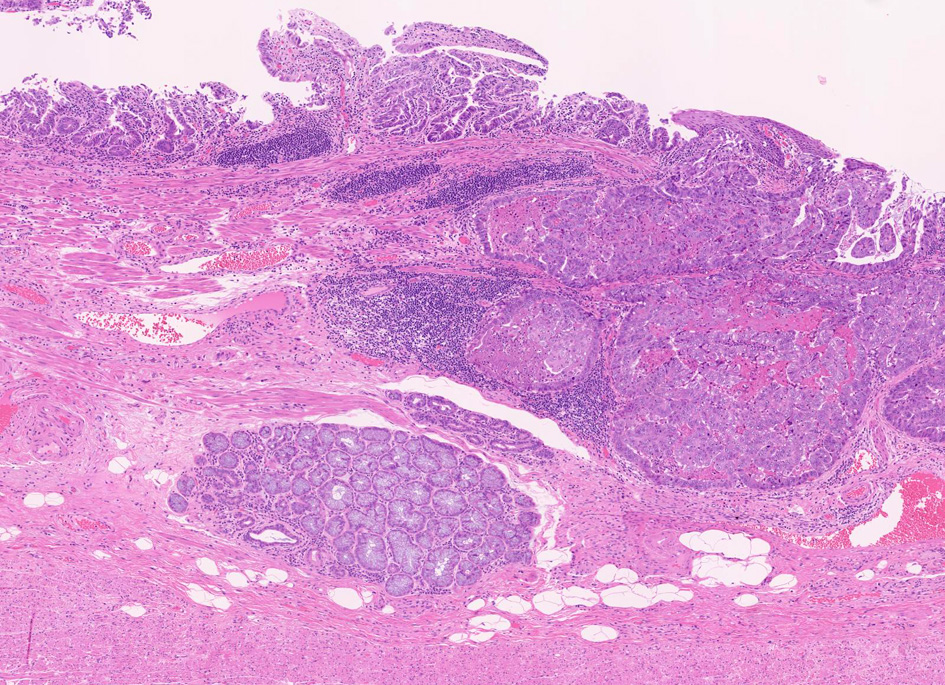

Barrettca01.jpg

Fig.1 Barrett食道 腺癌Fig.2 EGP